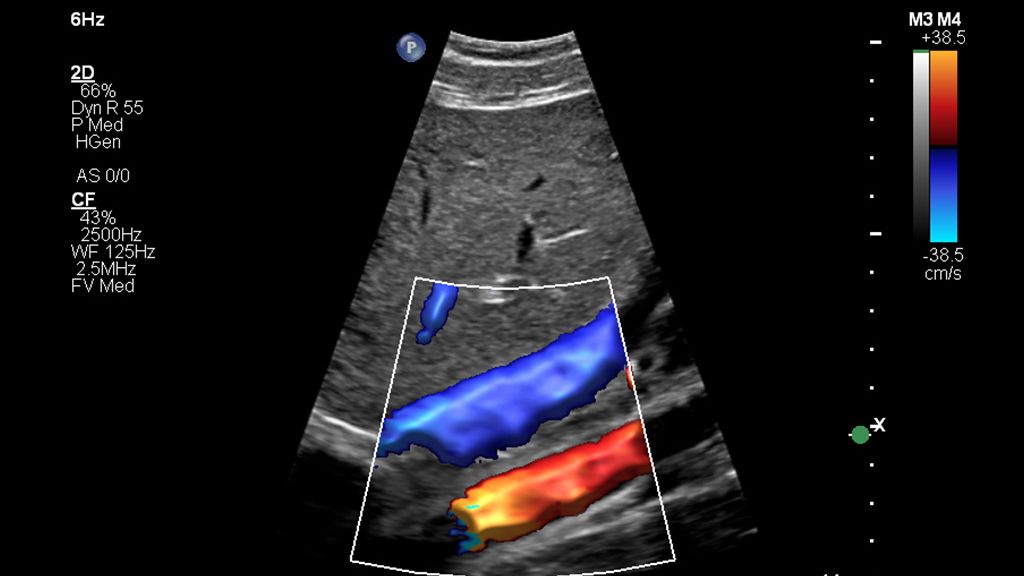

The widespread use of this technology in a general population could be helpful in screening for advanced chronic liver disease, especially considering that a complete study can be done in under three minutes using a non-invasive method for chronic liver disease.